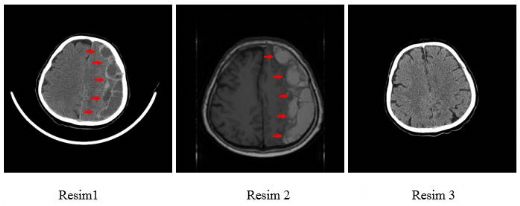

Tanı YöntemleriTravmaya bağlı beyin kanamasının tanısında çeşitli yöntemler kullanılmaktadır: